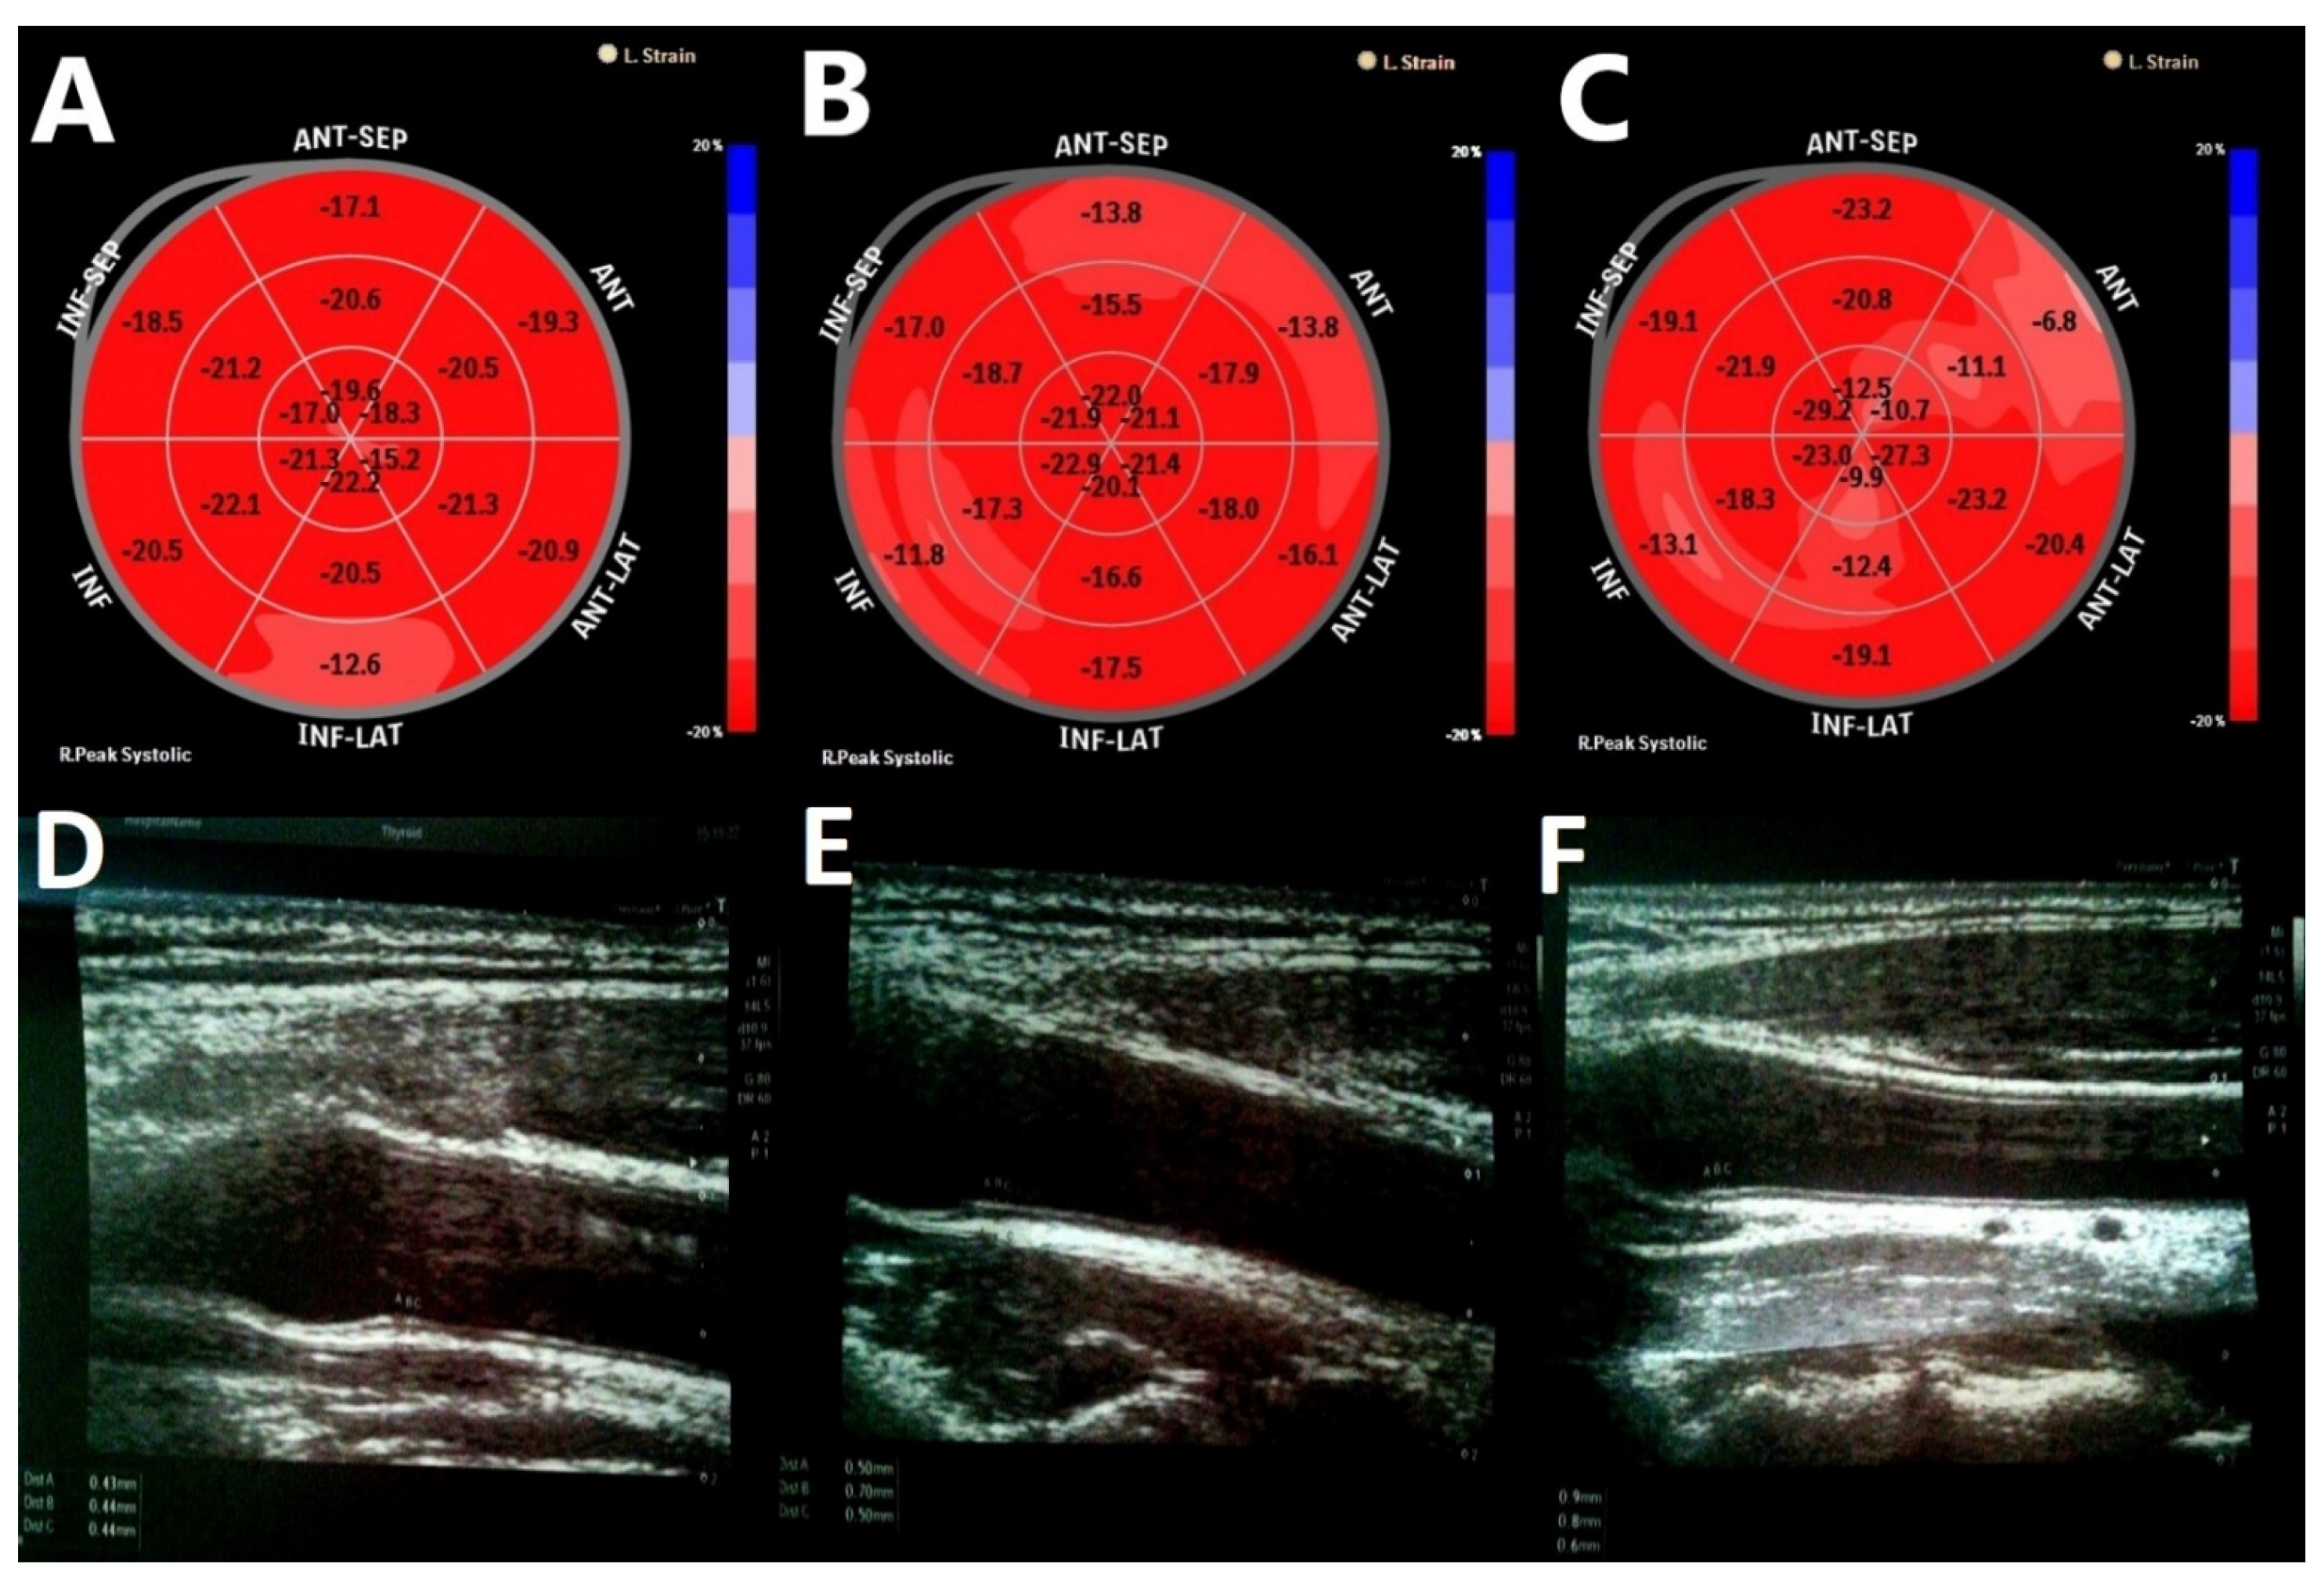

| LV GLS | 17.59 ± 1.97 | 16.90 ± 2.12 | 18.32 ± 1.53 | 18.96 ± 2.50 | 0.054 | 0.025 |